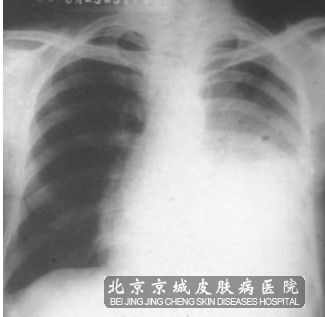

肺部鳞状*癌通常被称为肺鳞癌,肺鳞癌是肺癌较常见的组织学的类型,是发生在肺(支气管)的上皮性肿瘤,并且恶性的程度比较的高,在镜下观察多见为*角化和(或)*间桥。

肺鳞癌的癌*通常间的主要起源于叶支气管、段支气管和亚段支气管,因此肺鳞状*癌多属中央型,也有少部分的肺鳞状*癌属周围型。另外肺鳞癌的发作多为单发;亦有多发。肺鳞癌生长较腺癌相比要快,但发生转移的时间比腺癌要晚,晚期的鳞癌多发生于肺门淋巴结和纵隔淋巴结的转移,但向远处发生转移的比较少见。其中中老年、男性、嗜烟者为高危人群,它的发生主要与烟龄和每天吸烟量相关。